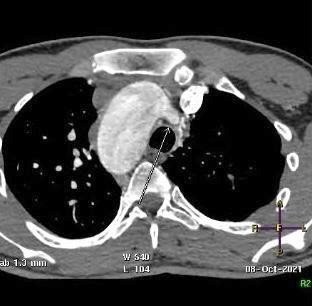

CT angiogram of chest shows complex cardiac disease including right-sided aortic arch (Figure 1), ventricular septal defect and overriding aorta (Figure 2). Non-visualization of the pulmonary trunk (Figure 3).

Figure 1: Contrast-enhanced axial CT chest at the level of the aortic arch showing right sided aortic arch.